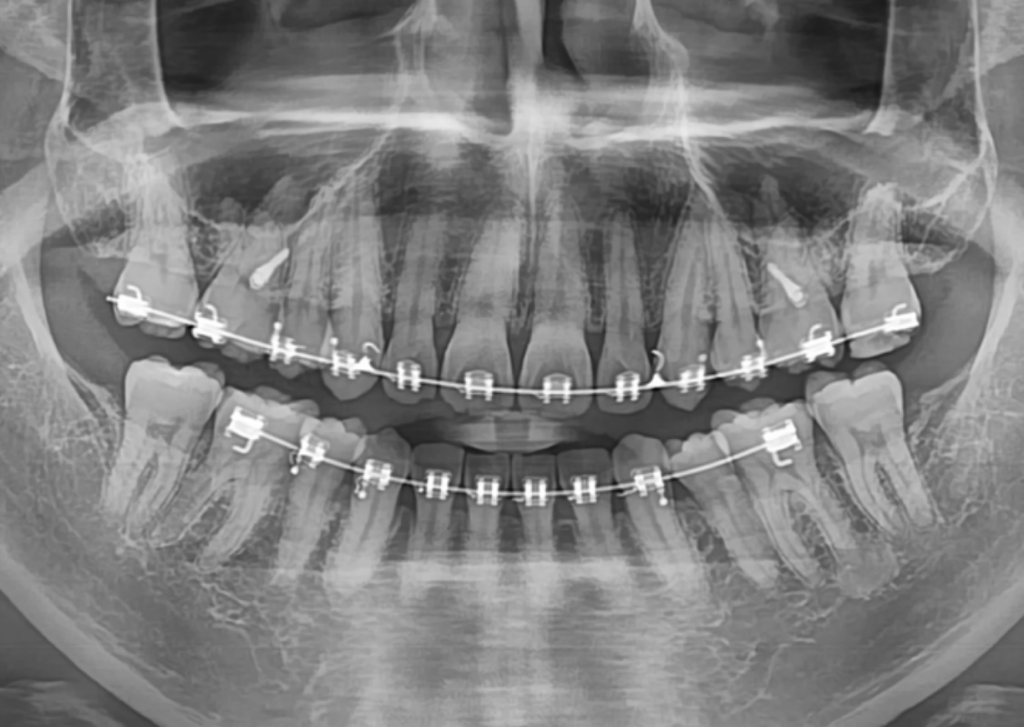

제 치근 길이가 짧은편인지 궁금해용

다른 사람 엑스레이와 비교했을때 유독 치근이 짧은 느낌이라 걱정이 되서요.. 많이 짧은편인가요?

엑스레이 상으로 딱히 크게 짧아보이지는 않습니다. 교정치료 마무리 후에 한번더 체크해보시는 게 좋습니다.

사진으로 봤을 경우에는 치아에 뿌리가 짧은 것으로 보이진 않습니다.

교정을 하는 과정에서 교정력이 치아에 너무 강하게 작용한다면 치약 뿌리가 흡수되는 경우가 있습니다 해당되는 증상은 사진만으로는 보이지 않는 것으로 생각됩니다.

치아 뿌리가 크게 짧거나 하진 않습니다. 교정을 하시는 중이신거 같은데 교정으로 인해서 부작용이 생기지 않으면 크게 문제가 되진 않을꺼 같습니다.

교정치료의 부작용으로 치아의 뿌리(치근)가 짧아질 가능성도 있습니다. 다만, 위 파노라마 방사선 사진만 보고는 정확히 치아의 뿌리가 짧아졌는지 확인이 불가능합니다. 아래 앞니의 뿌리가 남들보다 좀 짧은게 아닌지 걱정하실 수도 있는데 아래 앞니가 앞으로 각도가 기울어져 있다면 파노라마 방사선 사진에서는 굉장히 짧게 보이기도 합니다.